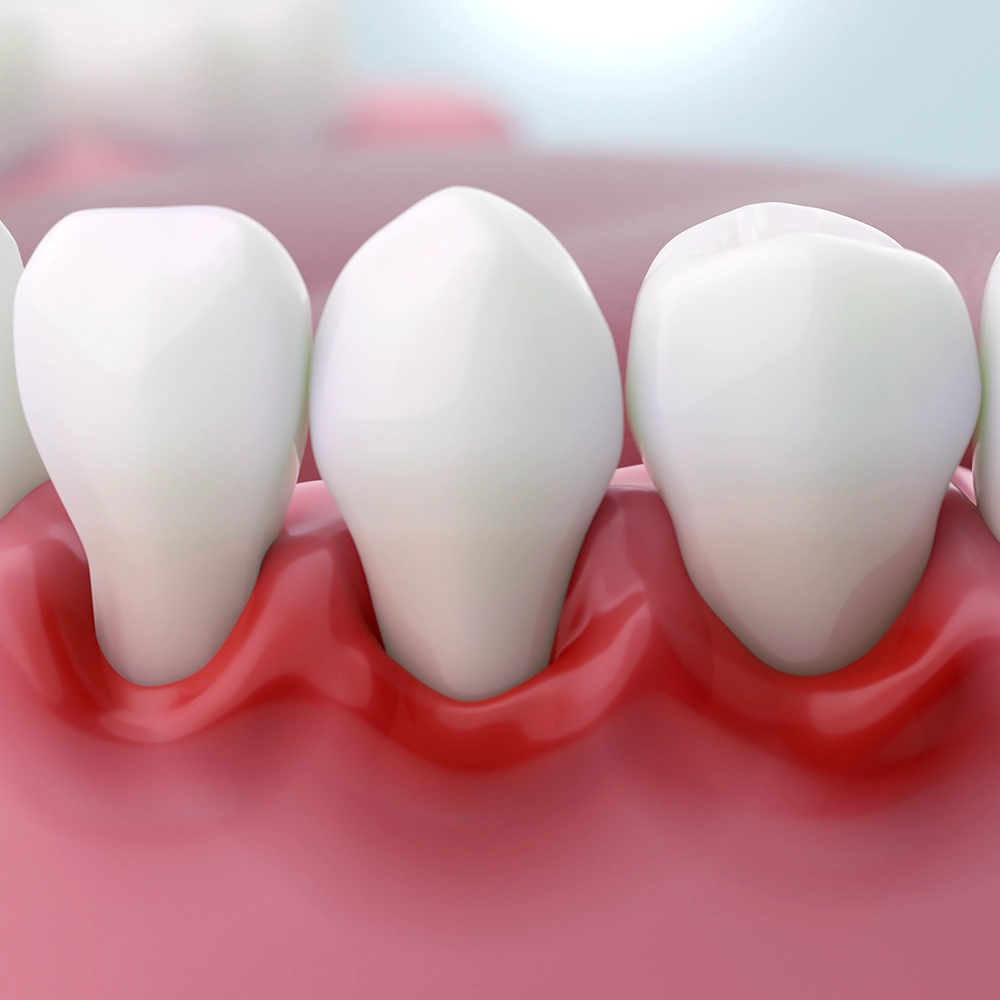

Stealthy Symptoms

Gum disease often starts quietly as gingivitis, with subtle signs like slight bleeding during brushing or mild gum redness. Ignoring these early symptoms can allow the disease to progress into periodontitis, a more severe condition that can threaten tooth stability. Catching it early is crucial to prevent more serious issues.

A detailed 3D rendering of a segment of gums showing healthy teeth juxtaposed against inflamed gums, illustrating the effects of gum disease and the importance of oral hygiene.

• Early signs include gums that bleed easily, especially during brushing or flossing, red or swollen gums, persistent bad breath, and receding gum lines.